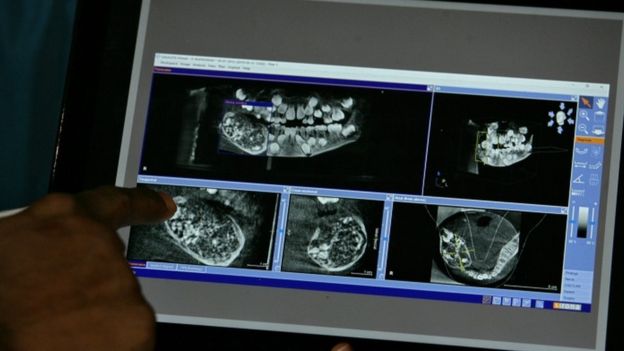

پزشکان پس از مشاهده عکس‌های رادیوگرافی دهانی متوجه دندان‌های غیرعادی در دهان این کودک شدند. صدها دندان در کیسه‌ای زیر دندان آسیا در فک پایین این پسر وجود داشت. پزشکان موفق شدند در یک عمل جراحی در بیمارستان چنای این کیسه را که حاوی صدها دندان‌ها بود خارج کنند. این دندان‌ها در اندازه‌های مختلف بودند.